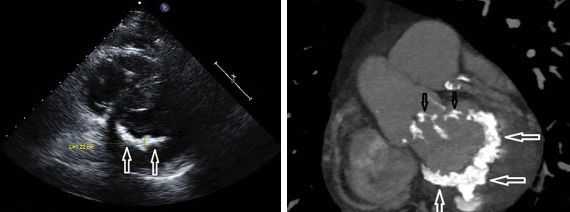

При эхокардиографии в M-модальном и двухмерном режимах могут быть обнаружены косвенные признаки недостаточности трёхстворчатого клапана: дилатация и гипертрофия правого предсердия и правого желудочка, возможны парадоксальные движения межжелудочковой перегородки и систолическая пульсация нижней полой вены.

Допплерэхокардиография позволяет обнаружить прямые и достоверные признаки трикуспидальной регургитации. В зависимости от степени недостаточности струя регургитации определяется в правом предсердии на различной его глубине, иногда достигает нижней полой вены и печёночных вен. Следует помнить, что у 60–80% здоровых лиц также определяется незначительная регургитация крови из правого желудочка в правое предсердие, однако максимальная скорость обратного тока крови при этом не превышает 1 м/с.